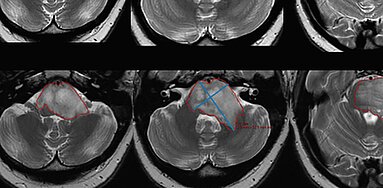

Using data from a large cohort of individuals without radiological tumor burden, researchers from University Hospital Cologne have conducted a study [1] aiming at establishing guidance values for…